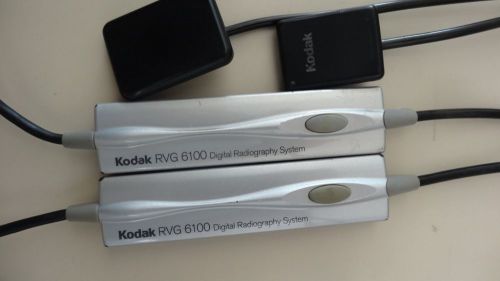

Kodak 6100 digital Xray sensors size 1 & 2